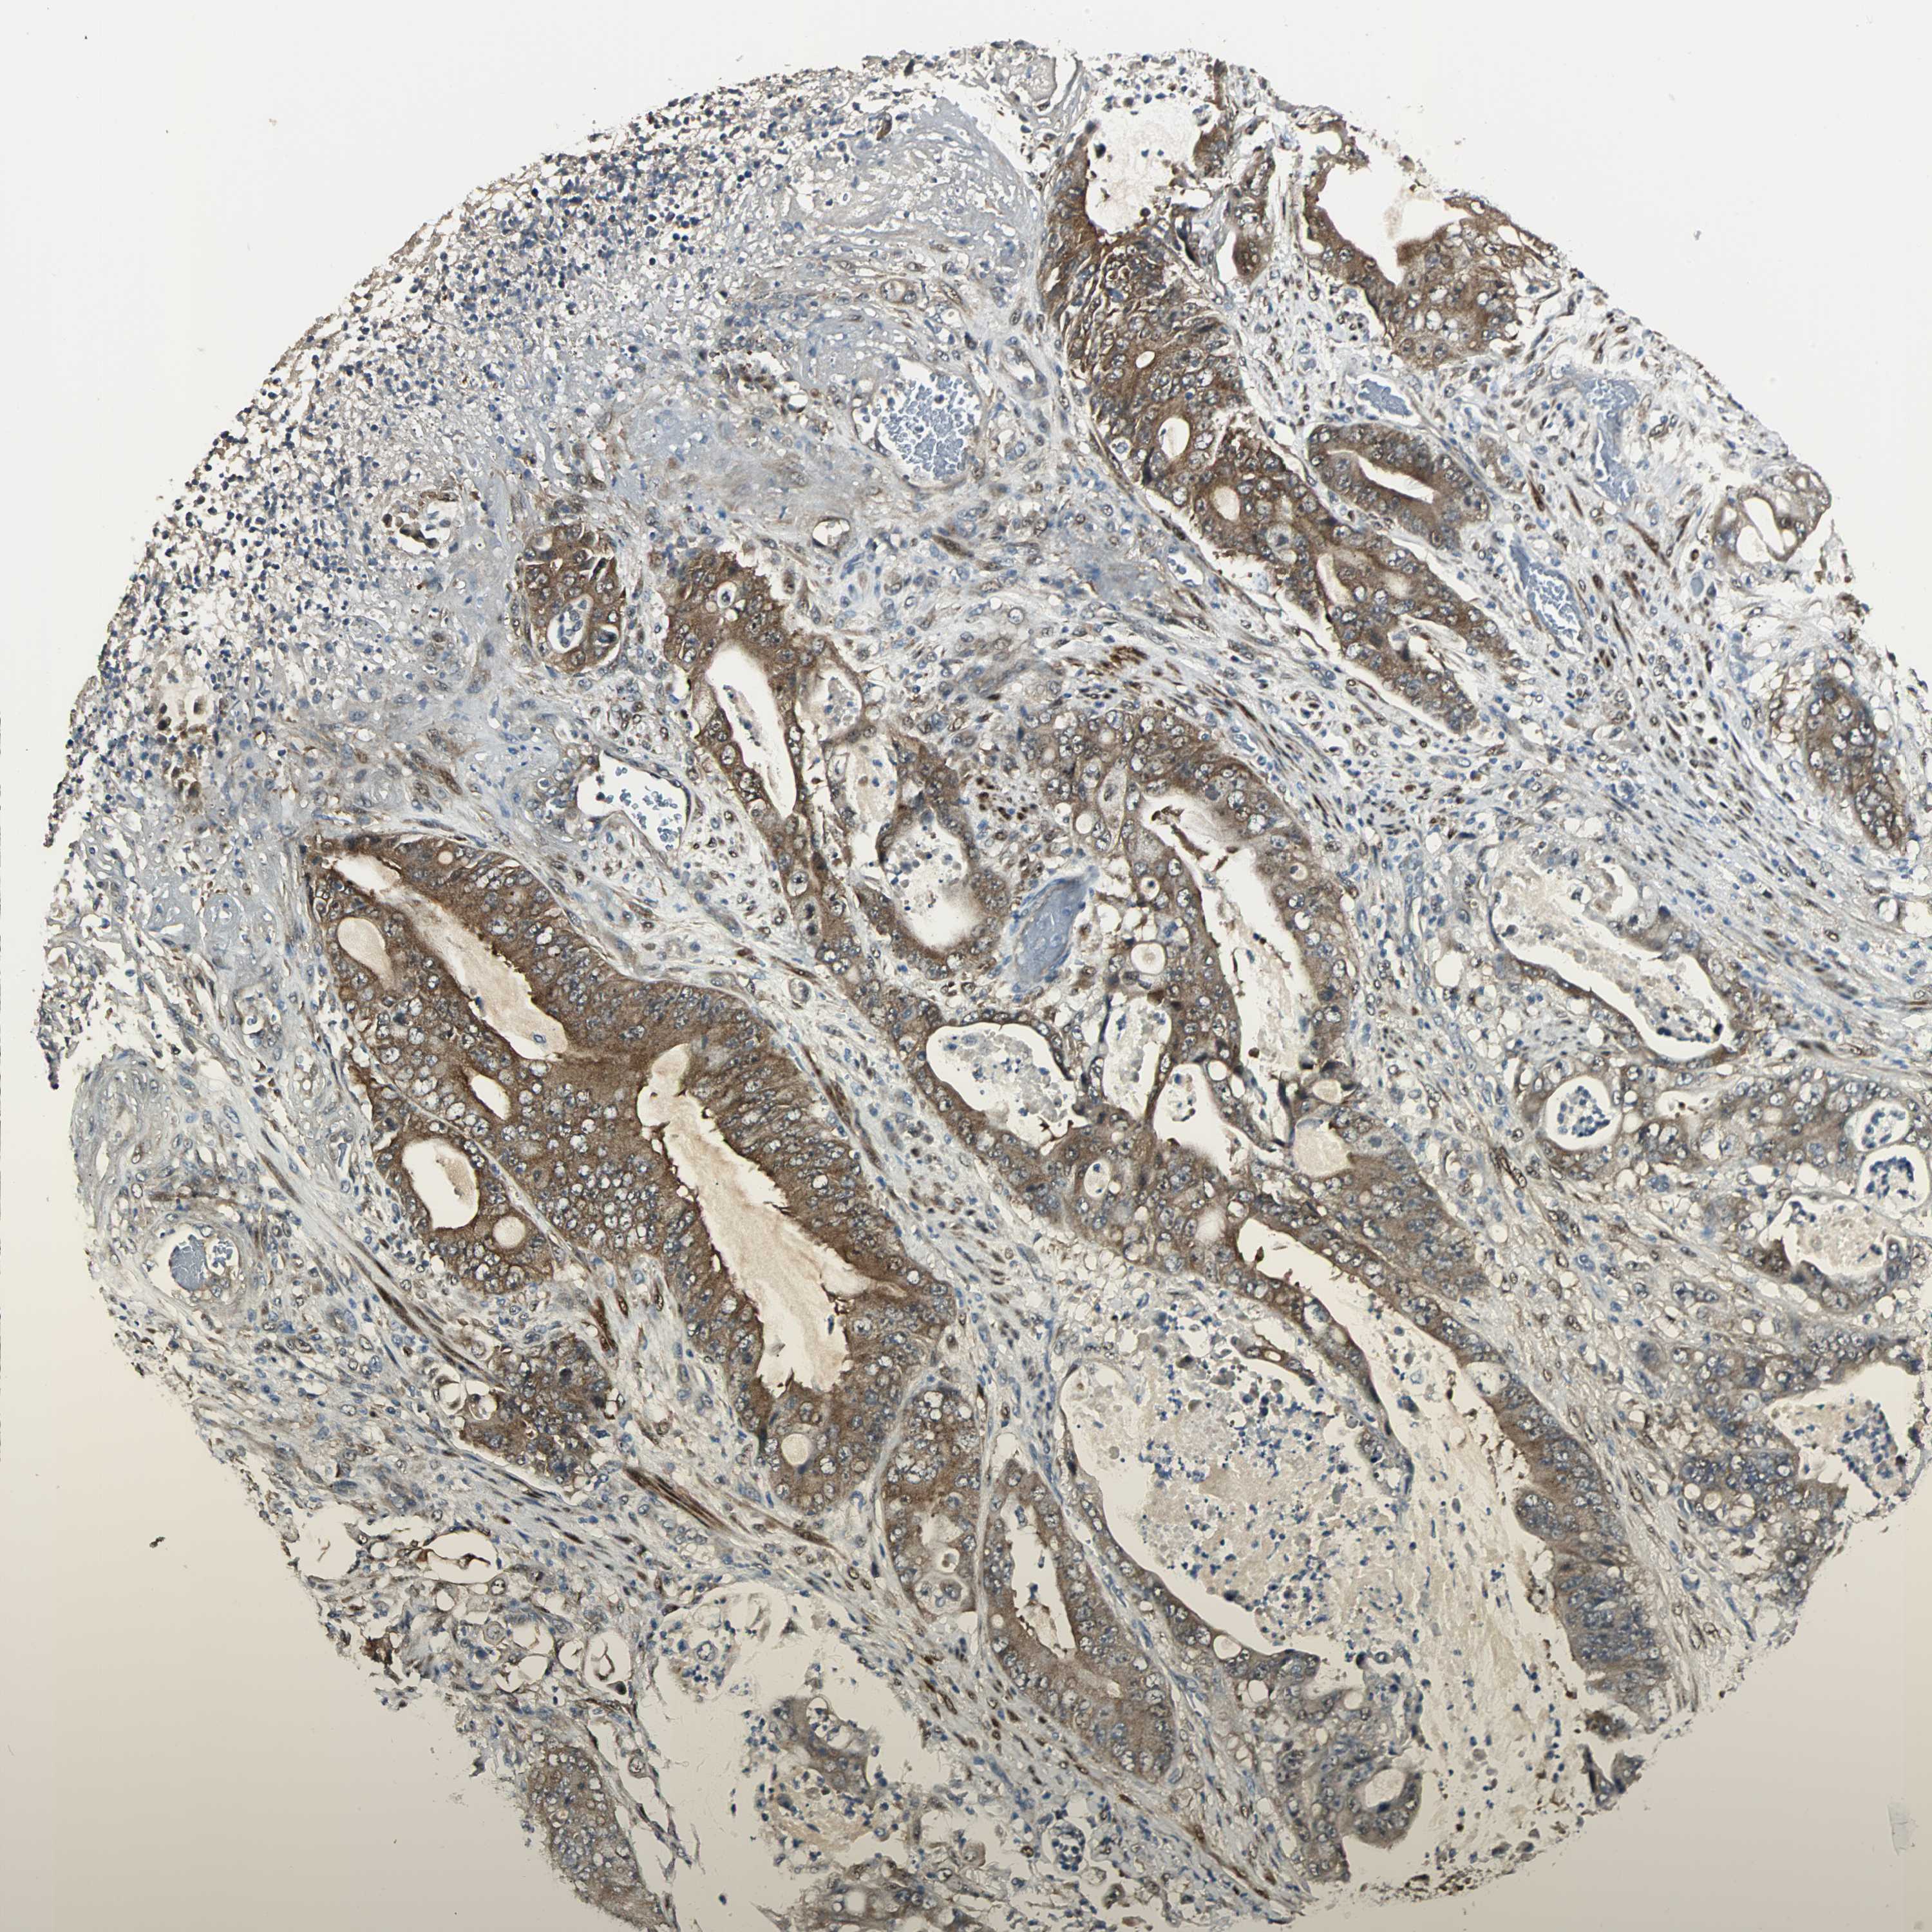

STOMACH CANCER - Protein expressioni

A mouse-over function shows sample information and annotation data. Click on an image to view it in a full screen mode. Samples can be filtered based on level of antibody staining by selecting one or several of the following categories: high, medium, low and not detected. The assay and annotation is described here.

Antibody stainingi

Antibody staining in the annotated cell types in the current human tissue is reported as not detected, low, medium, or high, based on conventional immunohistochemistry profiling in selected tissues. This score is based on the combination of the staining intensity and fraction of stained cells.

Each image is clickable and will lead to virtual microscopy that enables deeper exploration of all samples and also displays staining intensity scores, fraction scores and subcellular localization as well as patient and tissue information for each sample.

Antibody HPA005922

Antibody HPA006028

Antibody CAB008368

Staining

High

Medium

Low

Not detected

Intensity

Strong

Moderate

Weak

Negative

Quantity

>75%

75%-25%

<25%

None

Location

Nuclear

Cytoplasmic/membranous

Cytoplasmic/membranous,nuclear

Adenocarcinoma, NOS

Adenocarcinoma, High grade